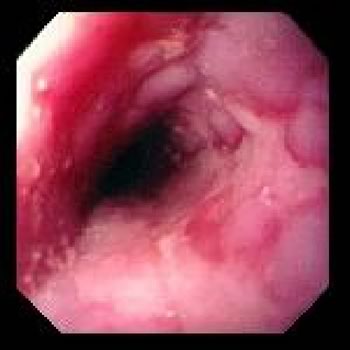

- EGDS: è l’esame più indicativo se positivo, poiché “vede” direttamente lo stato della mucosa esofagea e fornisce quindi anche una stima della gravità del problema (Figure 3, 4, 5). Può tuttavia risultare falsamente negativo nei soggetti che hanno assunto terapia antiacida per lungo tempo, fino a poco prima di eseguire l’esame (si veda al proposito l’articolo “Perché si sbaglia” sul M&B cartaceo di questo mese). Evidenzia anche alterazioni anatomiche (ernia iatale).